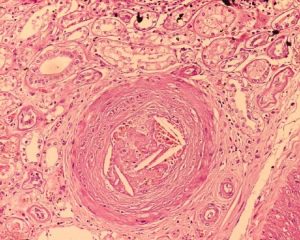

(Neuropatia periferica dolorosa-Immagine:Emboli di colesterolo. Credito immagine: Boonyarit Cheunsuchon, MD tramite Flickr, CC BY-NC 2.0). La chemioterapia può indurre una neuropatia periferica…